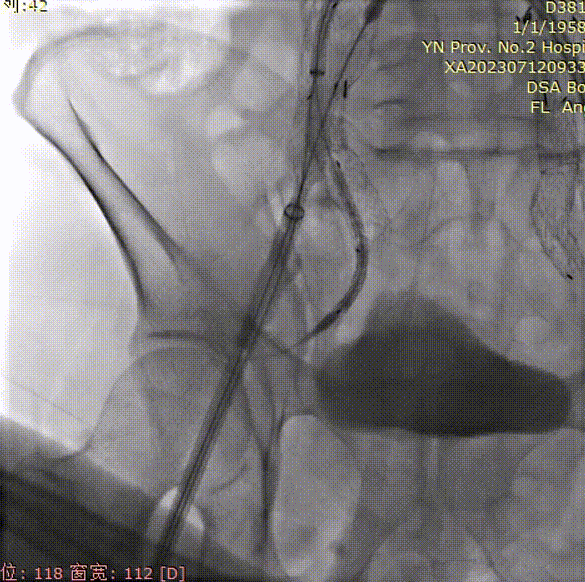

导管内手推造影,确认右髂内超选成功;

gore医疗怎么样「漫腹精论」双股动脉入路,纯腔内保双髂——GORE® EXCLUDER® 髂动脉分支型覆膜支架(IBE)治疗双侧髂总动脉_https://www.jmylbn.com_新闻资讯_第23张

右髂内支架通过IBE短腿后,整体往下拉IBE,将IBE短腿拉至右髂内动脉开口上方;